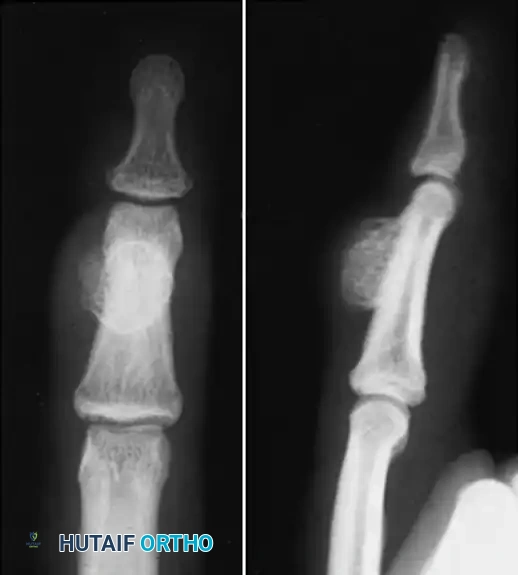

Anteroposterior radiograph demonstrating erosion at the base of the fourth metacarpal and distal capitate.

Sagittal section view revealing an intraarticular ganglion bridging the carpometacarpal joint with extensions into the substance of the capitate and fourth metacarpal.